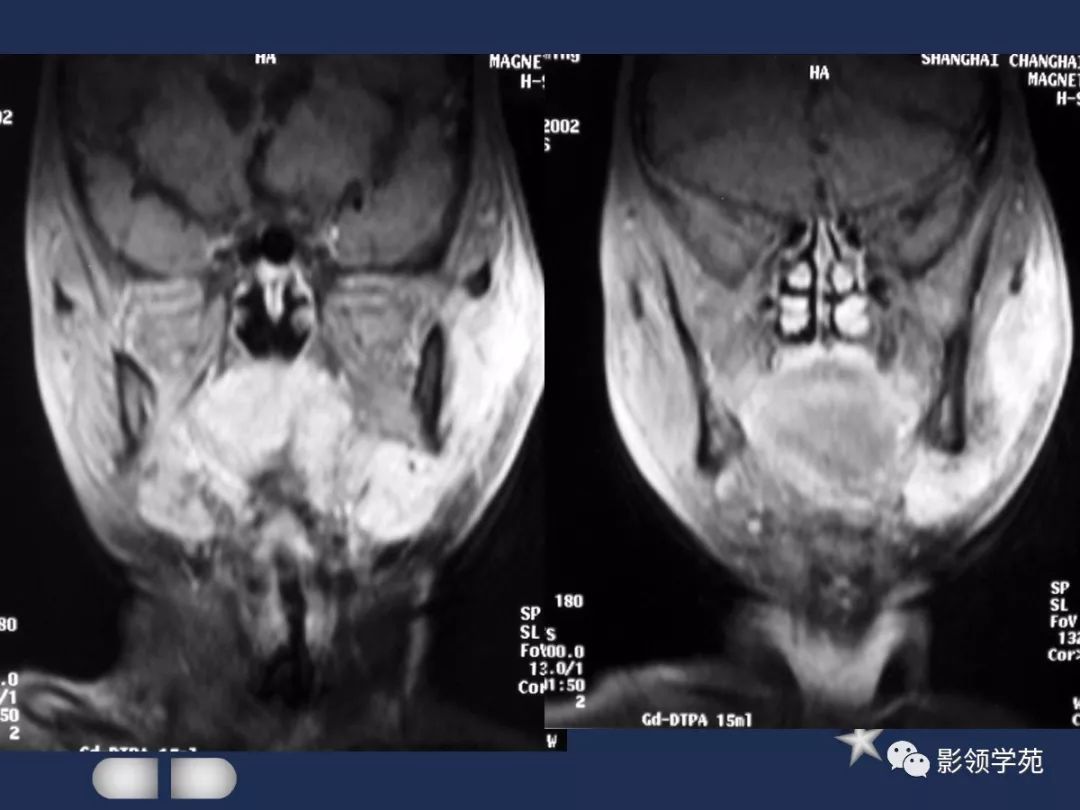

腮腺常见疾病影像诊断

- 腮腺混合瘤

- 腮裂囊肿

- 腮腺恶性肿瘤

MRI表现

- MRI上实性肿块在T1WI上呈等低信号,在T2WI上呈高信号,囊变区呈长T1长T2信号,钙化在T1WI及T2WI上均呈低信号。